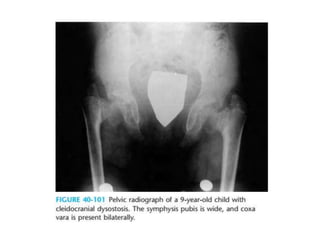

symphysis pubis is widened and vertical hypoplastic iliac wing

CLEIDOCRANIAL DYSPLASIA.

Cleidocranial dysostosis • Disorderin which the bones formed by intramembranous ossification (primarily the clavicles,cranium, and pelvis) are abnormal • Autosomal dominant • Chromosome 6 • Identified within the first 2 years of life

• 122.

• Elfin faces(the skull is wider than normal, but the face appears small ) • most common defect is U/L or B/L loss of the lateral end of the clavicle, with failure of development of the middle third of the clavicle second in frequency • second metacarpal is unusually long

enlarged cranium, widened sutures,and a persistent anterior fontanel

symphysis pubis iswidened and vertical hypoplastic iliac wing